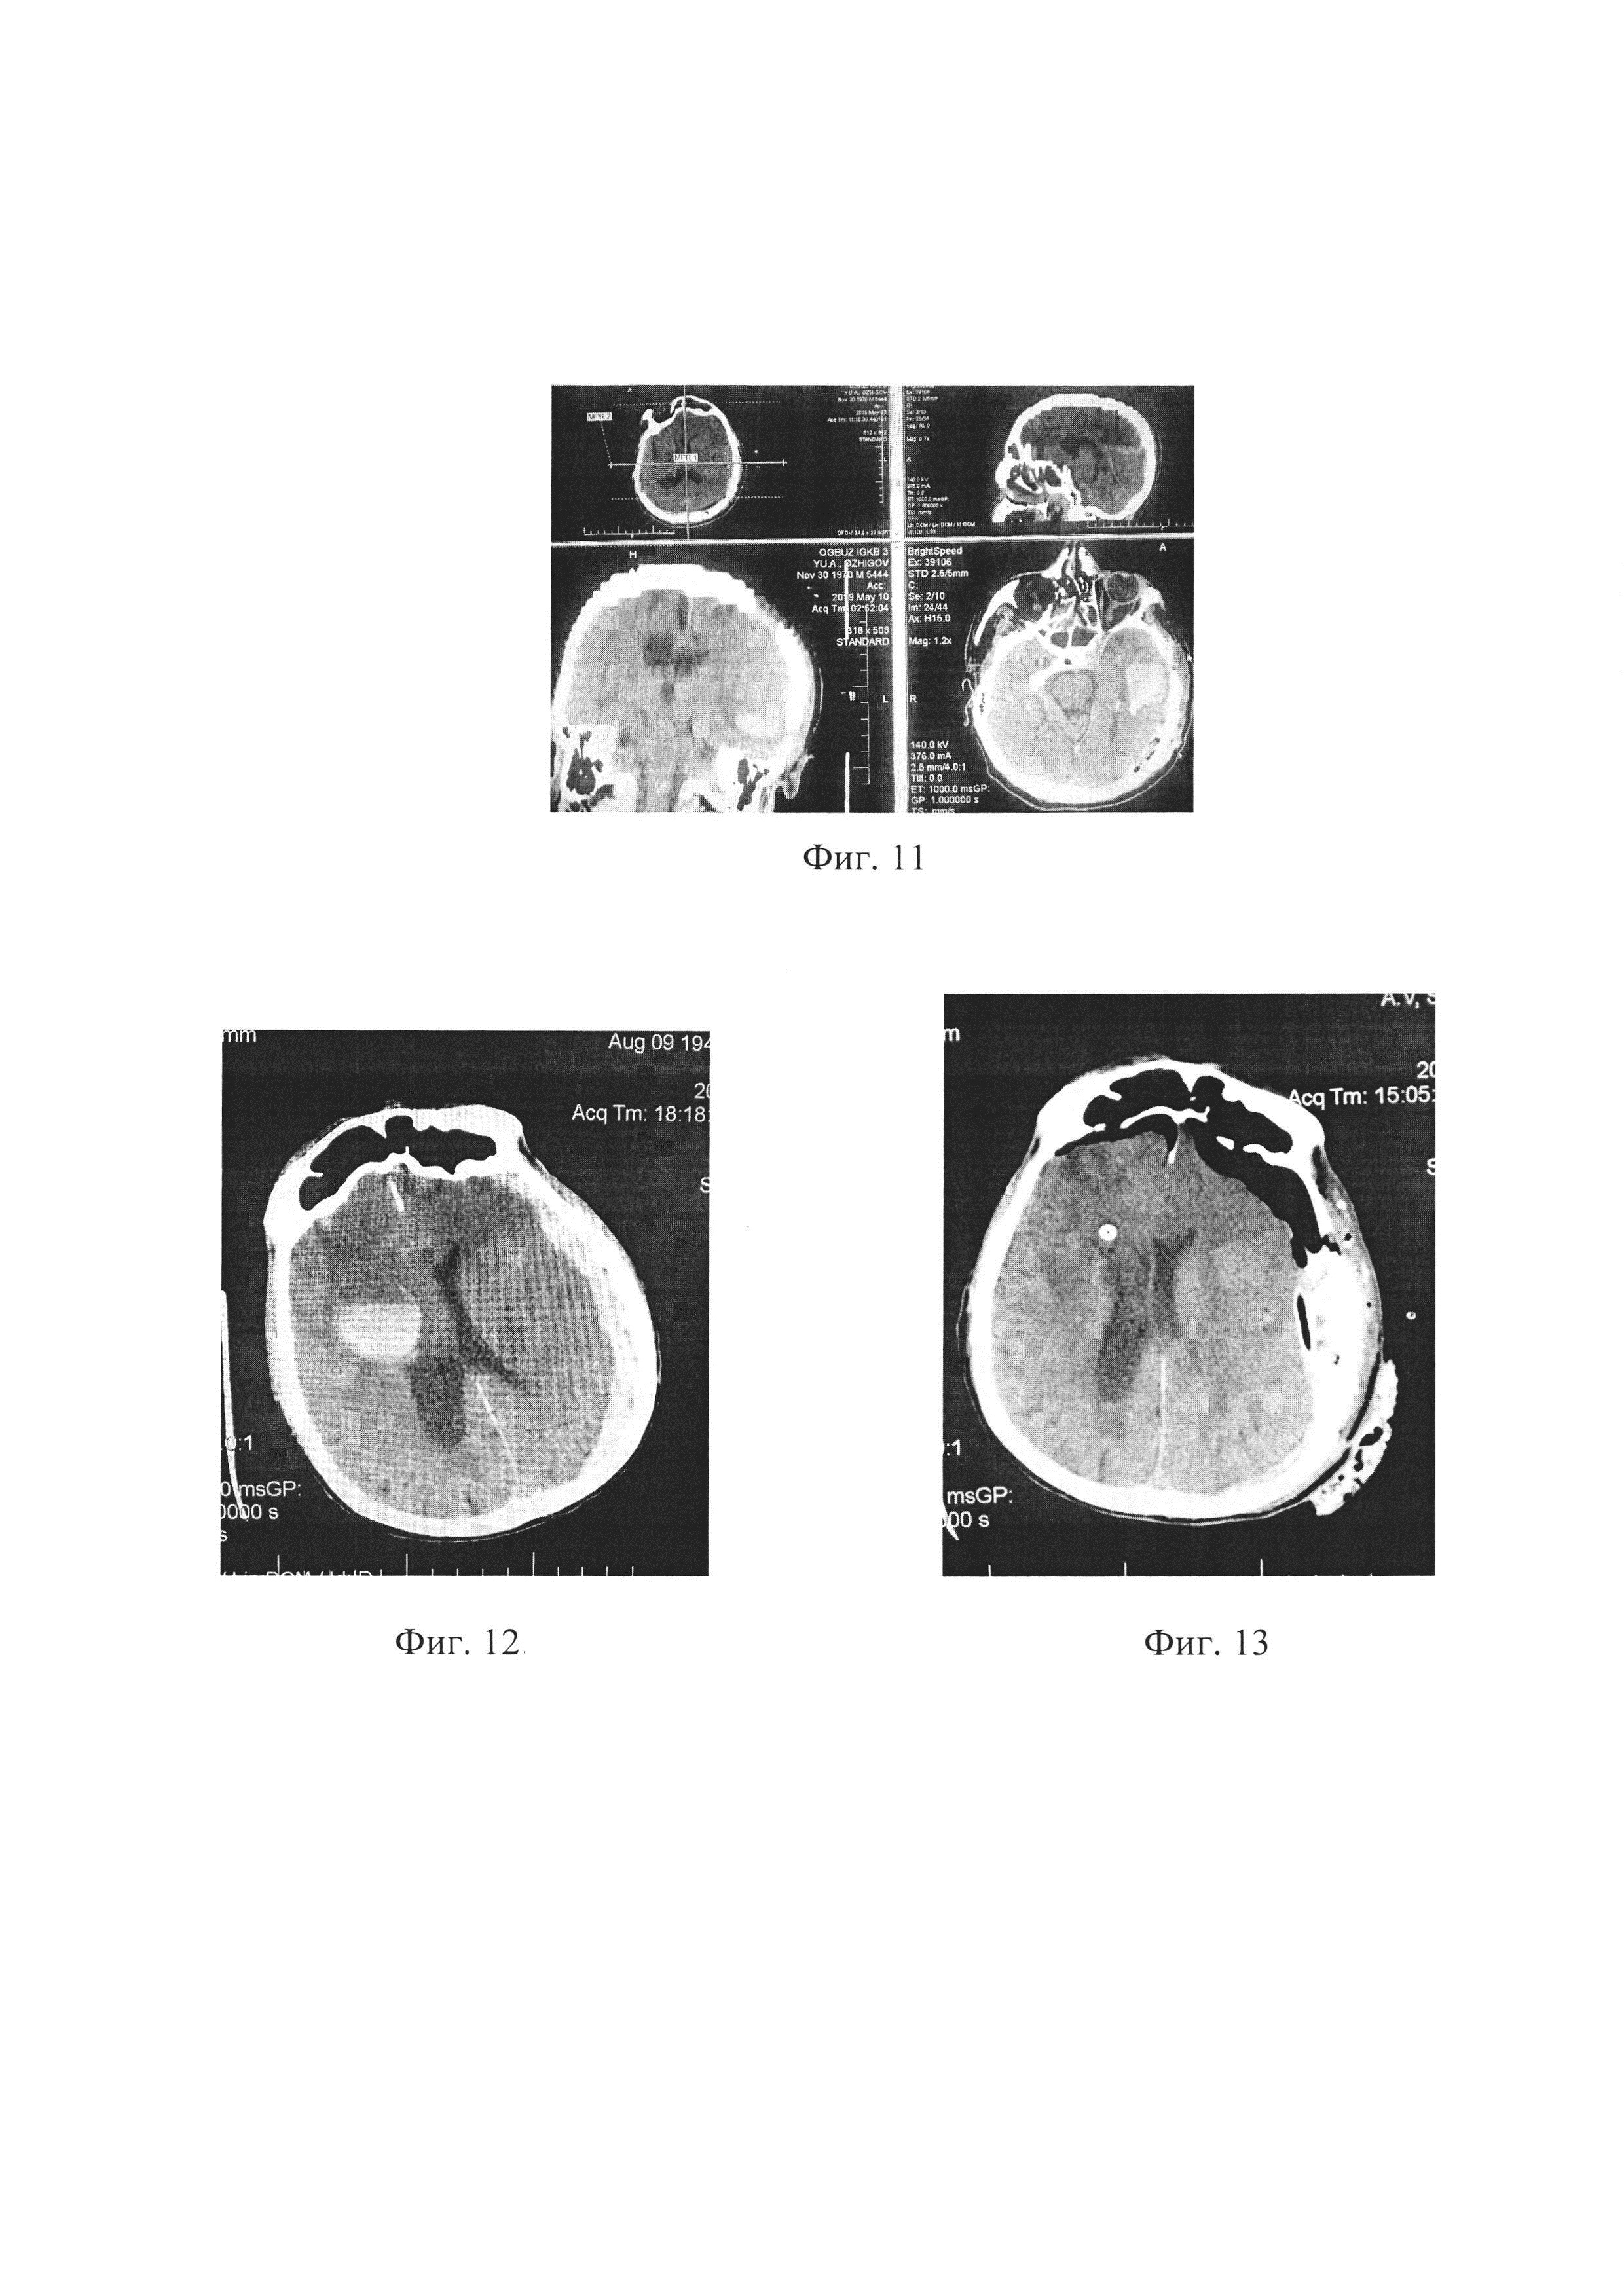

[84]

По жизненным показаниям и в связи с эпидуральной локализацией гематомы выполнена операция: КПТ в теменно-затылочной области с обеих сторон; удаление ОЭГ. Во время операции ревизия эпи- и субдурального пространств, отмечена выраженная «гипотензивная» реакция мозга в виде его «западения». Отсроченное кровоизлияние интрапаренхиматозно в левой височной доле диагностировано на 3 сутки после хирургического лечения (фиг. 11). В послеоперационном периоде пациент с положительной динамикой, выписан на амбулаторное лечение через 1 месяц после госпитализации.